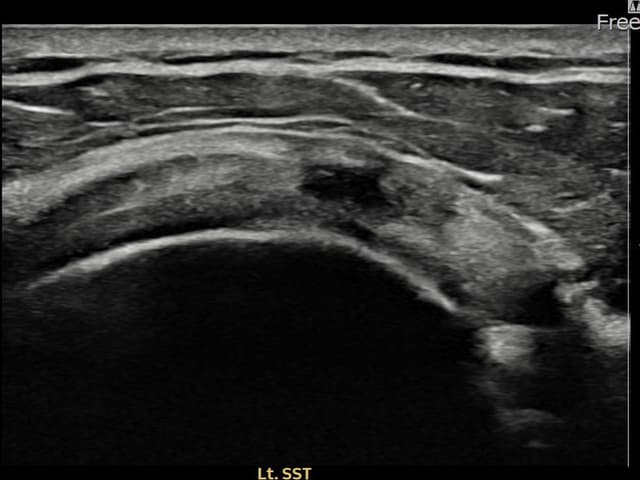

[経過期間: 23.07.18~23.09.14]

[縫縮術] 超音波検査にて左 棘上筋腱 광범위 部分断裂(15mm × 6mm (腱厚の約70%欠損))を確認。縫縮術施行後、腱の連続性が回復し、日常生活に復帰されました。